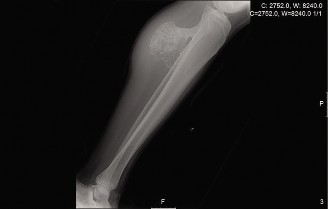

A 15-year-old female is diagnosed with Ewing sarcoma of the tibia. Which of the following is true regarding t…